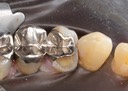

Gary Umeda #12-13